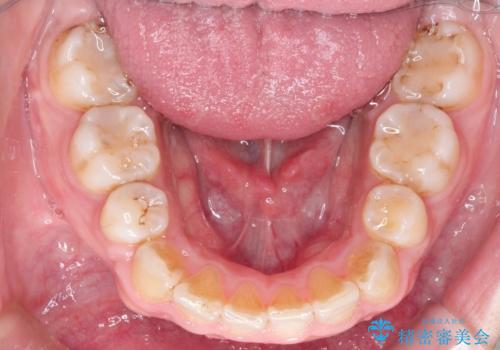

口元もすっきりとすることがで、口も自然に閉じるようになりました。

右上の歯は、歯並び的には前から4番目の歯を抜歯したかったのですが、5番目の歯がすでに治療してある歯でしたのでこちらの歯を抜歯しました。

これにより少し治療期間が延びてしまいましたが、健康な歯を残すことができました。